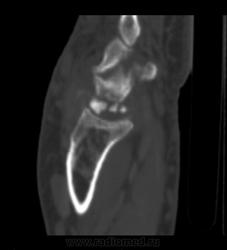

После 6-го коммента добавляю КТ. DICOM тут: http://files.mail.ru/A64E4C объём 14,5 МВ.

К большому моему сожалению, методом КТ не владею. Попробую описать то, что вижу, в надежде, что Вы поправите. Множественные полиоссальные очаги костной деструкции с достаточно четкими контурами (склеротический ободок?), местами с нарушением целостности кортикального слоя. В головчатой кости в деструктивном очаге плотная тень, похожая на секвестр. Полулунная фрагментирована соответственно ас/некрозу. Суставные щели сохранены, хотя соотношения костей запястья в горизонтальной плоскости выглядят не нормально. Мягкие ткани увеличены в обЪеме, дифференцировка структур по ладонной поверхности сохранена, по тыльной поверхности ближе к локтефой четкость теряется, на этом фоне непонятные мне включения. + отмечается расширение сосудистых теней. Остеомиелит и флегмона остаются у меня под большим сомнением. И характерных для нейротрофических нарушений напластований тоже не вижу (возможно, еще не срок?). При РА таких деструктивных изменений не встречала, и остеопороз под ?. Хотелось бы узнать Ваш вариант, уважаемая ЛГ.

Интраоссальные "секвестры" в запятье, а их два, это интраоссальные тофусы. Глыбчатые аморфные образования по плотности больше хряща, но меньше обызвествления, - это тофусы в мягких тканях. Кистовидные изменения костей запястья, с истончением коркового слоя и его частичным прерыванием - характерно для подагры.

Фрагментация и выраженное уплотнение полулунной кости - исход болезни Кинбека, с удивительно слабо выраженными признаками ДОА. Пациент не помнит, чтоб в детстве-юности были проблемы с правой кистью... но кто знает, может, у него память избирательная)).

Дословно не помню, примерно так: по рентгенограммам написала в заключении фрагментацию и асептический некроз полулунной кости, кистовидные просветления головчатой и трехгранной кости (деструктивные?). По КТ в заключении: признаки последствия болезни Кинбека, подагрические тофусы мягких тканей, подагрические изменения костей запястья.